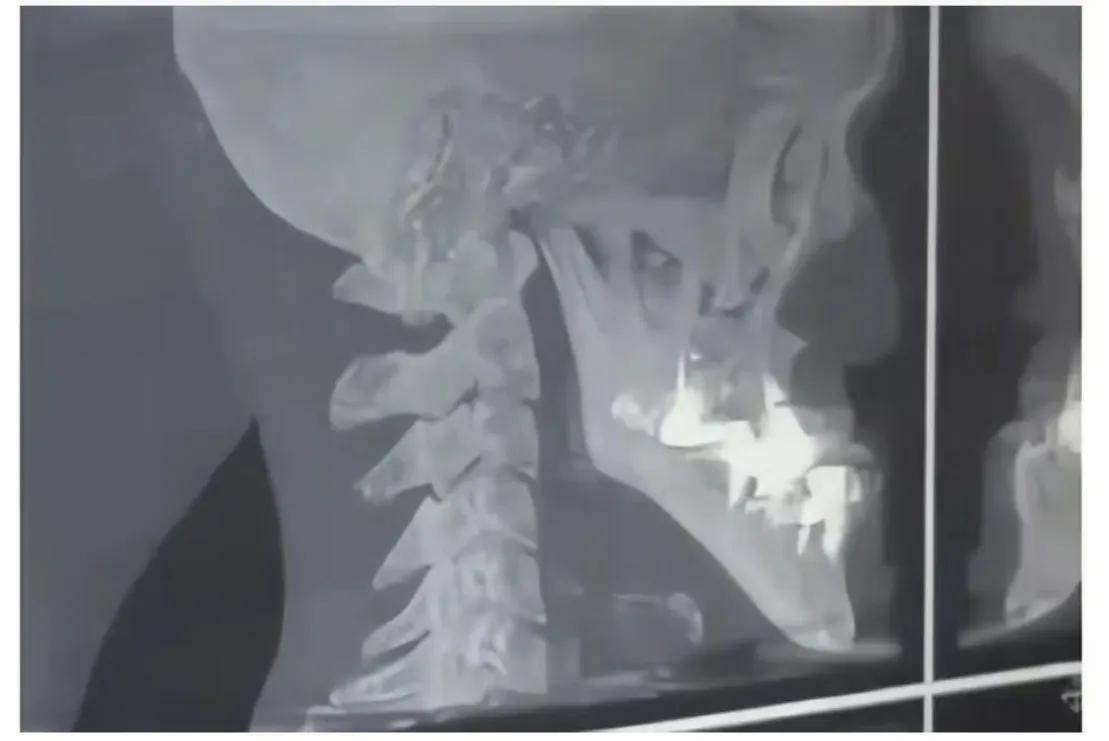

醫生又認為是牙齒和骨骼問題,結果拍片發現城之內一切正常,這就讓人百思不得其解了。

片子正常

城之內牙齒沒有問題,只是單純的下巴過長。